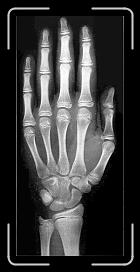

17 8 ANYS 10 MESOS